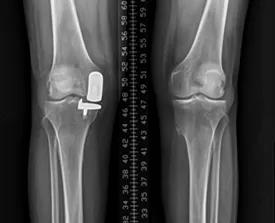

(二)膝骨关节炎单髁置换术

(四)膝关节置换术后关节翻修术